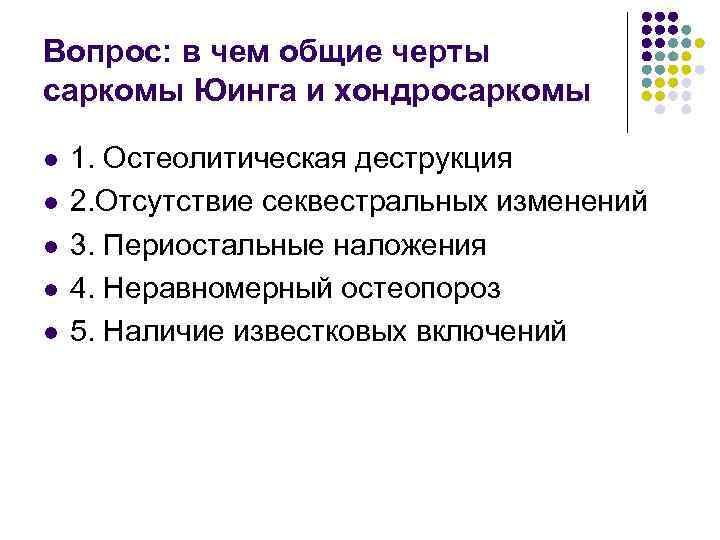

Вопрос: в чем общие черты саркомы Юинга и хондросаркомы l l l 1. Остеолитическая деструкция 2. Отсутствие секвестральных изменений 3. Периостальные наложения 4. Неравномерный остеопороз 5. Наличие известковых включений

Вопрос: в чем общие черты саркомы Юинга и хондросаркомы l l l 1. Остеолитическая деструкция 2. Отсутствие секвестральных изменений 3. Периостальные наложения 4. Неравномерный остеопороз 5. Наличие известковых включений

Ответ: l l Остеолитическая деструкция Отсутствие секвестральных изменений Периостальные наложения Неравномерный остеопороз

Ответ: l l Остеолитическая деструкция Отсутствие секвестральных изменений Периостальные наложения Неравномерный остеопороз